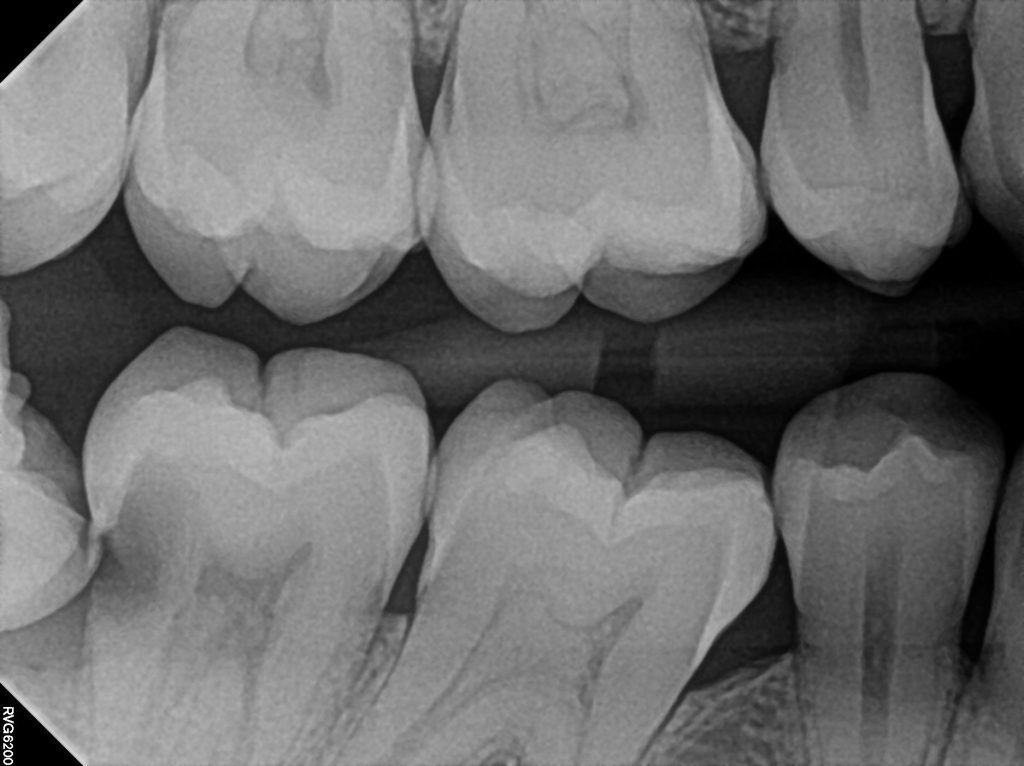

As a dentist, I often explain to patients that delaying wisdom tooth extraction can sometimes lead to consequences that are much more serious than the procedure itself. A recent case in our clinic illustrates this clearly.

One patient had been advised several times over the years to remove a wisdom tooth that was partially impacted and leaning against the neighboring molar. Because the tooth was not causing pain, the extraction kept getting postponed.

By the time the patient returned with discomfort, a large cavity had formed in the area where the wisdom tooth was pressing against the adjacent molar. Unfortunately, the decay had progressed so far that both teeth were affected. In the end, we had to remove the wisdom tooth and the neighboring molar as well, and the patient later required a dental implant to restore the missing tooth.

Cases like this highlight why dentists often recommend addressing problematic wisdom teeth earlier rather than waiting until symptoms appear.